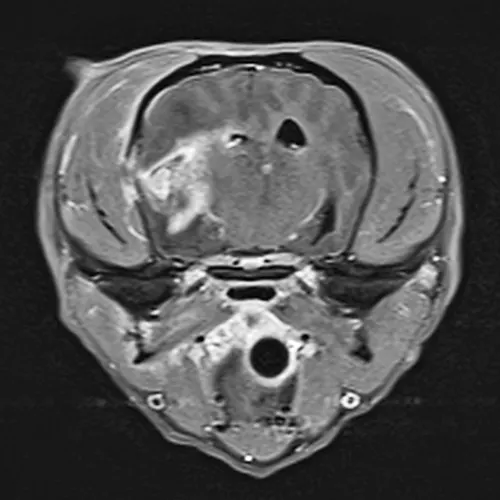

Figure 2

MRI showing postcontrast enhancement of a bacterial abscess and meningitis. There is also evidence of a fracture in the bone immediately adjacent to the abscess.